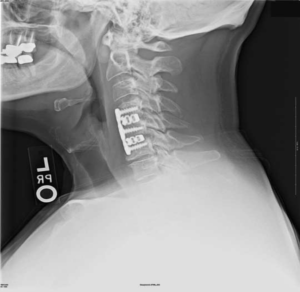

Импланты шейного отдела позвоночника на рентгене.

Представлены КТ пациента до и после оперативного лечения по поводу осложненного перелома пятого шейного позвонка. Выполнена корпорэктомия пятого шейного позвонка с комбинированным корпородезом аутокостью из подвздошного гребня и пластиной китайского производства.